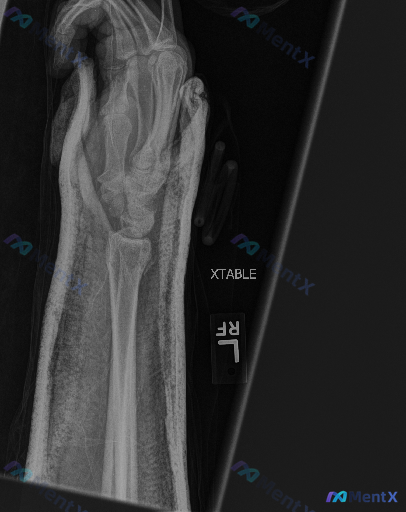

整理到一份右手前臂及手部X光斜位片的影像资料,背景是急性外伤后,主要影像表现如下: 1. 骨骼方面:桡骨远端可见明显骨折线,断端有移位及成角畸形,皮质连续性中断;尺骨茎突位置也见骨折断端,有移位;掌骨及近节指骨可见范围内未见明确骨折线。 2. 关节方面:腕关节解剖结构因骨折发生改变,关节面移位、对合...